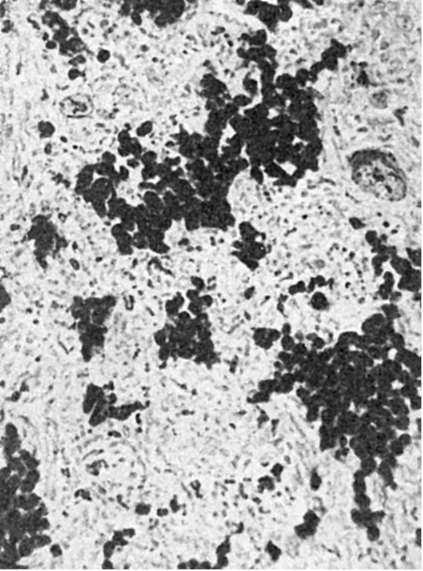

В зависимости от условий развития местный гемосидероз может возникать в пределах не только участка ткани (гематома), но и целого органа. Таков гемосидероз легких, наблюдающийся при ревматическом митральном пороке сердца, кардиосклерозе и др. Хронический венозный застой в легких ведет к множественным диапедезным кровоизлияниям, в связи с чем в межальвеолярных перегородках, альвеолах, лимфатических сосудах и узлах легких появляется большое число на- груженных гемосидерином клеток (см. Венозное полнокровие).

Гемосидероз легких. Цитоплазма гистиоцитов и альвеолярного эпителия (сидеробластов и сидерофагов) нагружена зернами пигмента